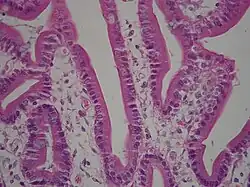

Histologists classify epithelia cells by appearence. Single layer epithelias is called 'simple'; multilayer is called stratified. The diagram below shows a typical histological classification. Plain light microscope appearances appear in the thumbnails to the right.

Transport Epithelia

These epithelia are found lining the tubes of the intestine and the kidney.

- The cells are usually columnar and regulate the exchange of nutrients an ions.

- The apical surface usually has microvilli, fingerlike projections that can increase the absorptive area up to 100X.

- These cells are usually bound together with tight junctions

- These cells usually have a high metabolism (numerous mitochondria)